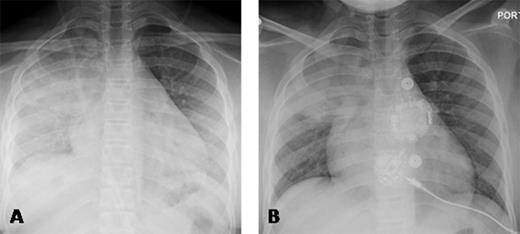

A 10 years old African American child with hemoglobin SC type SCD was transferred to our institution with fever and right upper lobe consolidation. Her respiratory rate was 23 breaths/min, SpO2 was 95% breathing room air. Serial CXR showed opacification of the entire right lung and part of the left lower lobe over a 12-hour period (Panel A). Because of the rapid progression, transfusion was recommended. However, because of the family's Jehovah's Witness religious faith, transfusion was refused.

PEG-COHb is in clinical development for the treatment of SCD and is designed to deliver preloaded carbon monoxide (CO), pick up O2, and deliver O2 to hypoxic tissue. PEG-COHb serves as a vasodilator and anti-inflammatory agent. It has been shown to have anti-sickling properties in vitro (ASH Abstract 1372, 2014). The agent was obtained from Prolong Pharmaceuticals via an emergency IND (16432) from the FDA. The agent was acceptable to the family and church elders. After written consent was obtained, 500 cc were infused according to dosing information obtained from Prolong Pharma. The CXR (Panel A) 3 hours before infusion shows opacification of the right lung and the left lower lobe. A CXR obtained one hour after infusion showed no worsening, and the CXR (Panel B) obtained 29 hours after Panel A shows significant improvement in the opacification of the lower lobes. The right upper lobe consolidation was likely bacterial pneumonia, and would not be expected to clear rapidly.

The rapid reversal of radiographic features consistent with progressive "pure ACS" secondary to the right upper lobe infectious process suggests that PEG-COHb may be an effective treatment for sickle cell related ACS.

Panel A demonstrates the chest x-ray 3 hours prior to PEG-COHb with right upper lobe consolidation and evolving bilateral lower lobe consolidation and Panel B 29 hours following administration of PEG-COHb demonstrating improvement in the lower lobes.